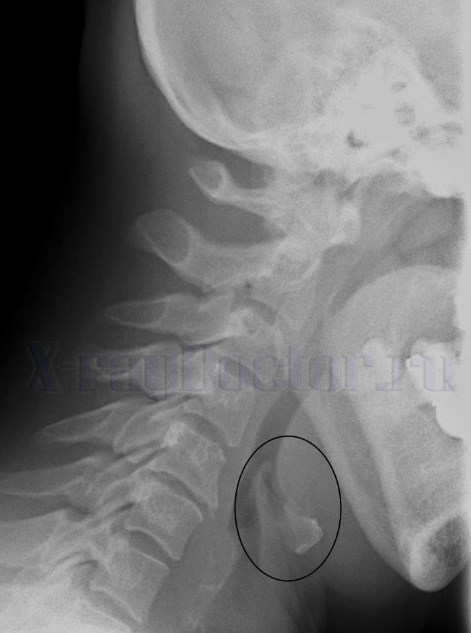

Вышеперечисленные структуры хорошо видны на боковой рентгенограмме.

Рентген-снимок показывает разные виды смещений органа в сочетании с изменениями надгортанника, корня языка и подъязычной кости.

Хрящевые структуры на снимке виды при их обызвествлении. Такие изменения наблюдаются обычно у людей в 70-80 лет.

Вначале обызвествляется щитовидный хрящ, затем перстневидный и черпаловидные связки.

Рентгенологическое обследование позволяет изучить морфологическое состояние органа, выявить сужения и деформации на пути следования воздушного столба. Рентгеновское исследование нередко позволяет выявить опухолевые образования и инородные тела.